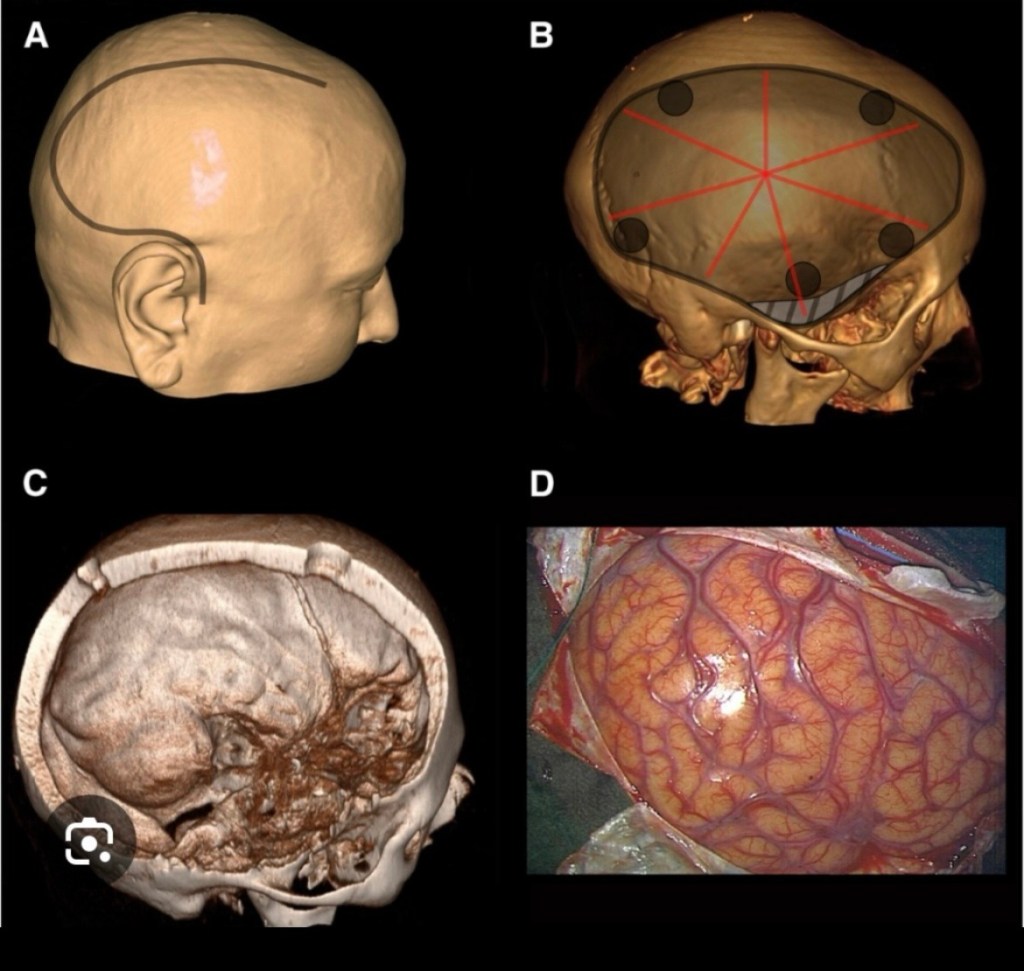

I learnt how to do craniotomies which unlike what is commonly believed about ‘brain surgery’ is fairly easy. First is to plan craniotomy according to the location of the lesion, then if possible to avoid crossing the midline as there’s the saggital sinus in the midline. The saggital sinus is a channel carrying venous blood enclosed by the dura mater. Also avoid going too posteriorly as the transverse sinus crosses there.

After planning the location of your craniotomy an incision has to be made on the scalp. This is in the form of a flap with a wide pedicle to prevent devascularisation or loss of blood supply to the scalp the flap preferably should be within the hairline as to be cosmetic.

Returning to the subject of crainotomies, once the location is planned and an incision is made in the scalp, holes called ‘burr holes’ are drilled on the skull in a polygonal pattern, either pentagonal, hexagonal, octagonal or nonagonal pattern depending on the size of the opening required. While drilling the holes the dura mater is not punctured.

C. Surface of dura exposed D. Surface of brain exposed

Then a Gigli saw wire is passed between adjacent holes and the intervening bone is cut. When all adjacent holes are connected a bony flap is raised having a polygonal shape. The advantage of having this bone flap was it could be replaced over the defect once the surgery was completed, avoiding the concave defect in the skull.

Once the skull is opened, depending on the pathology, either on the dura mater or on or within the brain, an opening can be made in the dura mater to expose the surface of the brain.

Once burr holes made in a polygonal pattern over the skull we next got to join them with a Gigli saw. The wire of the Gigli saw is threaded through one burr hole and brought through an adjacent burr hole. Then the handles are attached and the wire is moved in a to and fro motion. The wire cuts the bone smoothly and once all the holes are connected, we have a bone flap which can be lifted off.

When my lecturer became confident in my abilities to do a craniotomy he allowed me to do a craniotomy for a case of extra dural haematoma. After reviewing the CT Scan he instructed me to make a ‘trauma flap’ on the scalp and then do the craniotomy. He drew the trauma flap for me, which started from the forehead on one side without crossing the midline and ran parallel to the midline posteriorly, then took a curve downwards and returns to end just above the ear.